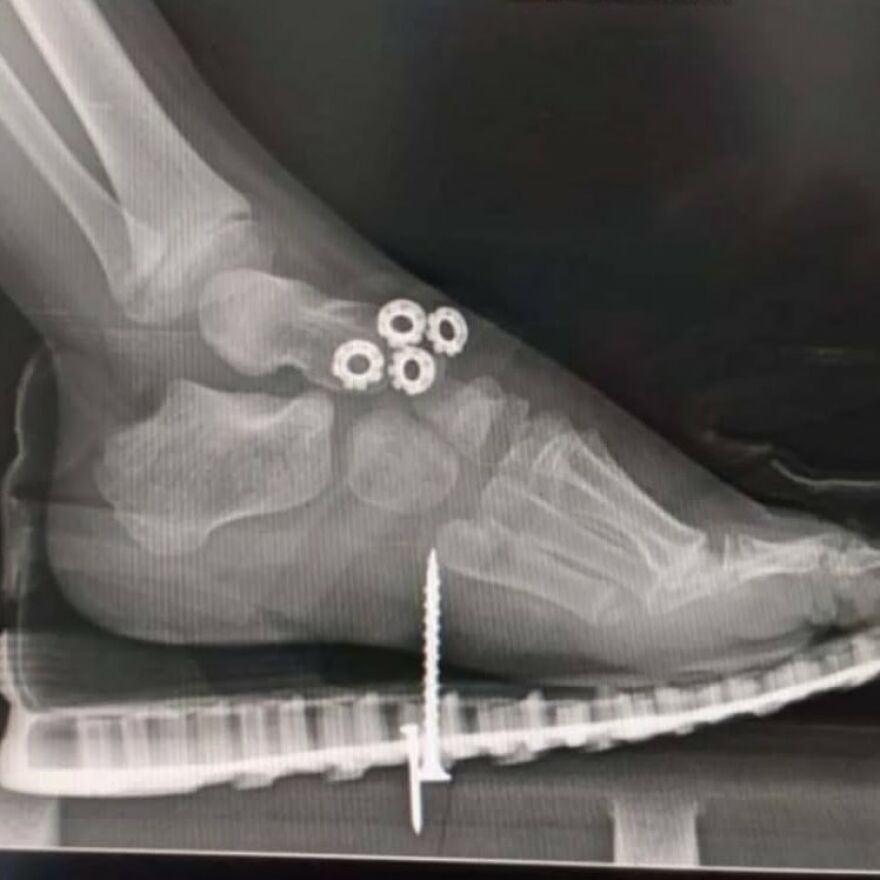

Looks like another" feet on the dashboard" of a car involved in an accident